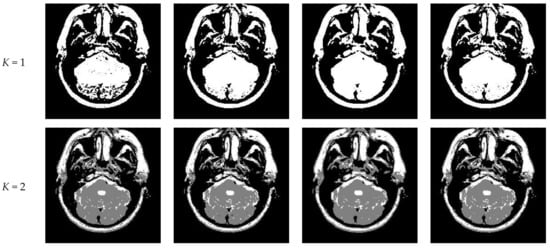

Figure 10 and Figure 11 display segmentation results of different algorithms for slice #042 and slice #082, respectively. For single level of thresholding K = 1, it can be observed that segmentation results obtained by the Otsu method have many fragmented small areas, such as the lower soft tissue in the first row of Figure 10a, whereas IIMT performs slightly better. However, the edges segmented by HL-IIMT and Proposed are much clearer. In the case of , it can be seen that Otsu and IIMT have similar segmentation effects. HL-IIMT and Proposed are better than Otsu and IIMT in terms of edge-preserving and denoising, as shown in the segmentation results in Figure 11 (K = 2, K = 4).

Figure 10.

Segmentation results obtained by different segmentation algorithms for slice #042 with number of thresholds K from 1 to 5: (a) Otsu, (b) IIMT, (c) HL-IIMT, (d) Proposed.